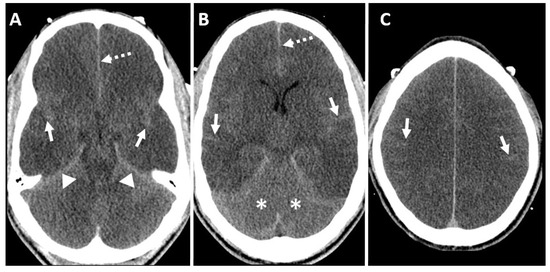

7.4. Computed Tomography (CT) Brain

7.5. Computed Tomography Angiography (CTA) Brain